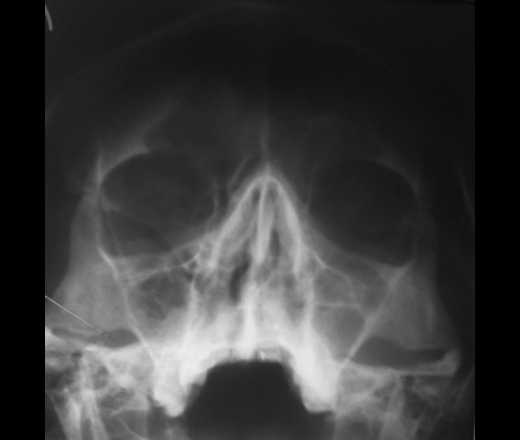

Направлен с диагнозом: синусит? Головная боль, субфебриллитет, соплюх. Качество снимка - мое, фирменное ... Обработала, как смогла.

... Обработала, как смогла.

фронтит, правосторонний верхнечелюстной синусит. контроль в динамике.

ЛОР посмотрел и ничего, кроме катарального ринита, не нашел...

ну лобные можно засомневаться, а вот в правой гайморовой точно ведь есть затенение ее нижних отделов.

По страшному снимку моему толком не видно, а вот на КТ множественные и разнообразные перегородки в пазухах видны хорошо. Я могу уверенно сказать только о следах жидкости в правой верхнечелюстной пазухе и субтотальном заполнении гомогенной жидкостью левой половины основной пазухи. Остальное, на мой взгляд, утолщение слизистой. Но на 100% утверждать не буду. В правой лобной я предполагаю (и только!) полипоз.